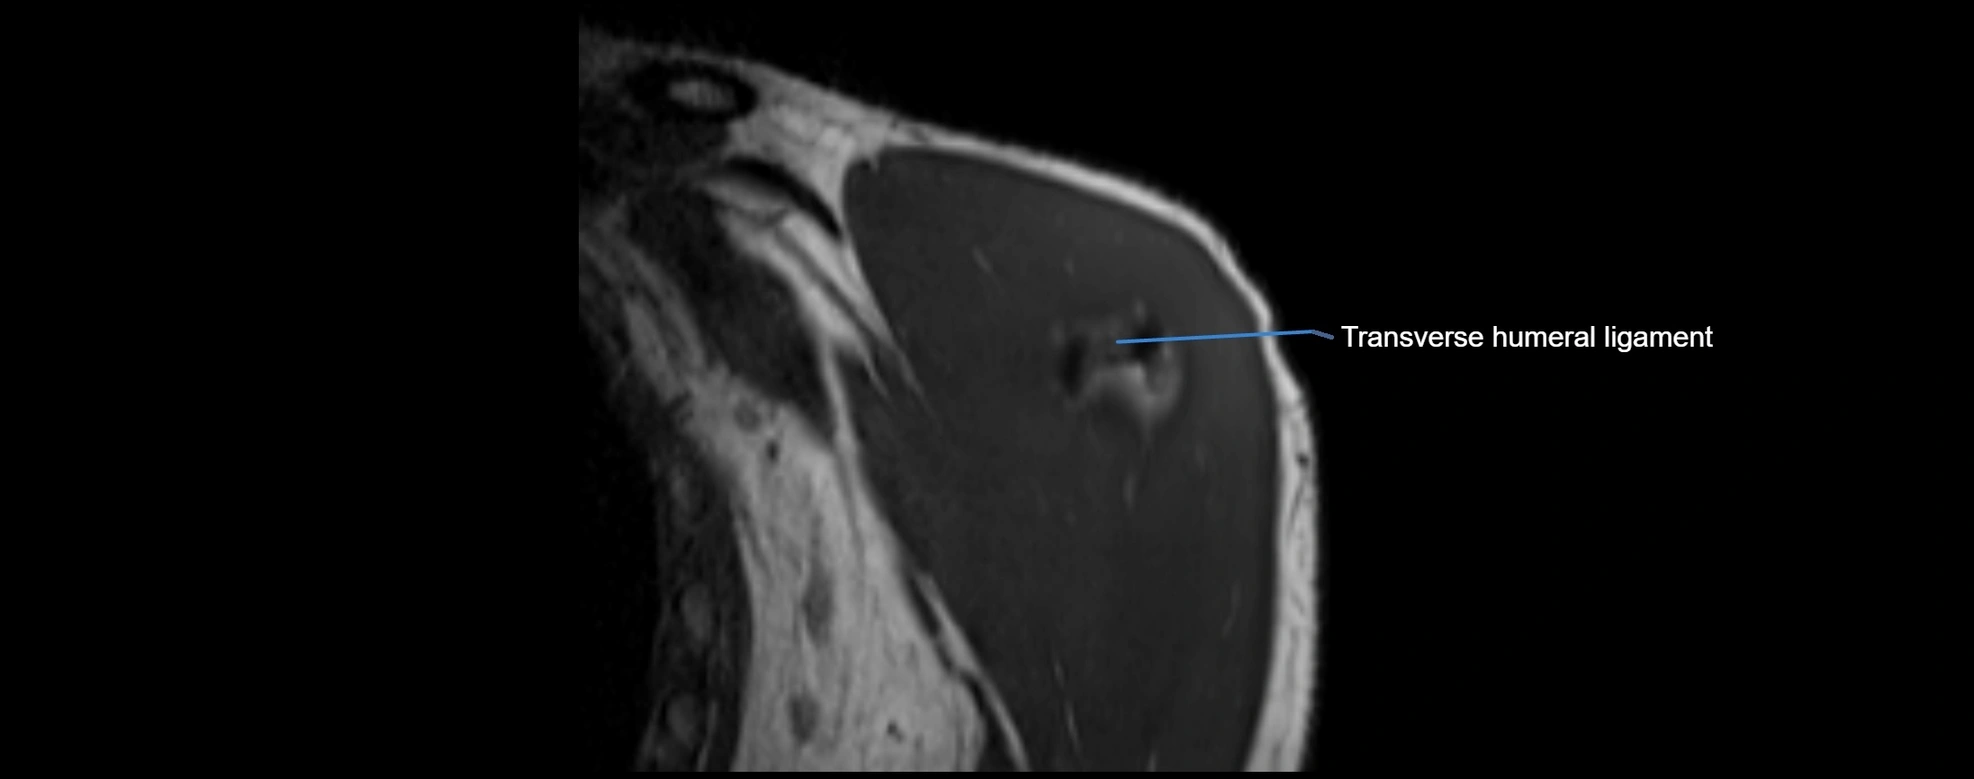

MRI images

image